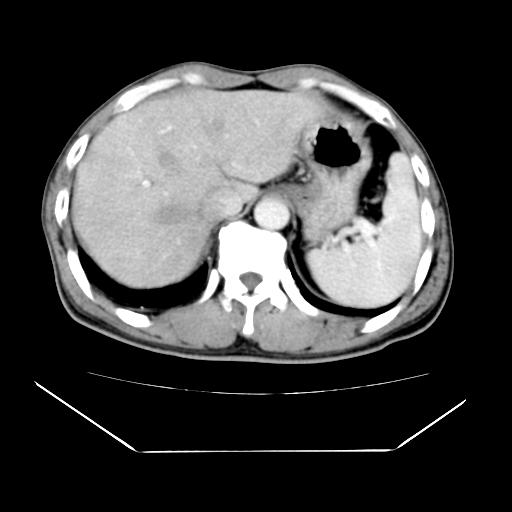

男性,55岁,外院体检afp明显升高,但b超未发现异常,否认乙肝病史。来我院ct增强。有延时扫描。

标题: 建议磁共振检查

延时扫描完全充填,血管瘤

肝脏右叶动脉期可见低密度影,至延迟期被充填,考虑血管瘤可能性大。

肝右叶病灶

不排除肝右叶肝癌可能。

如果这个是癌灶的话则下腔静脉有瘤栓可能

肝6段血管瘤

血管瘤可能性大。

考虑肝右静脉影。